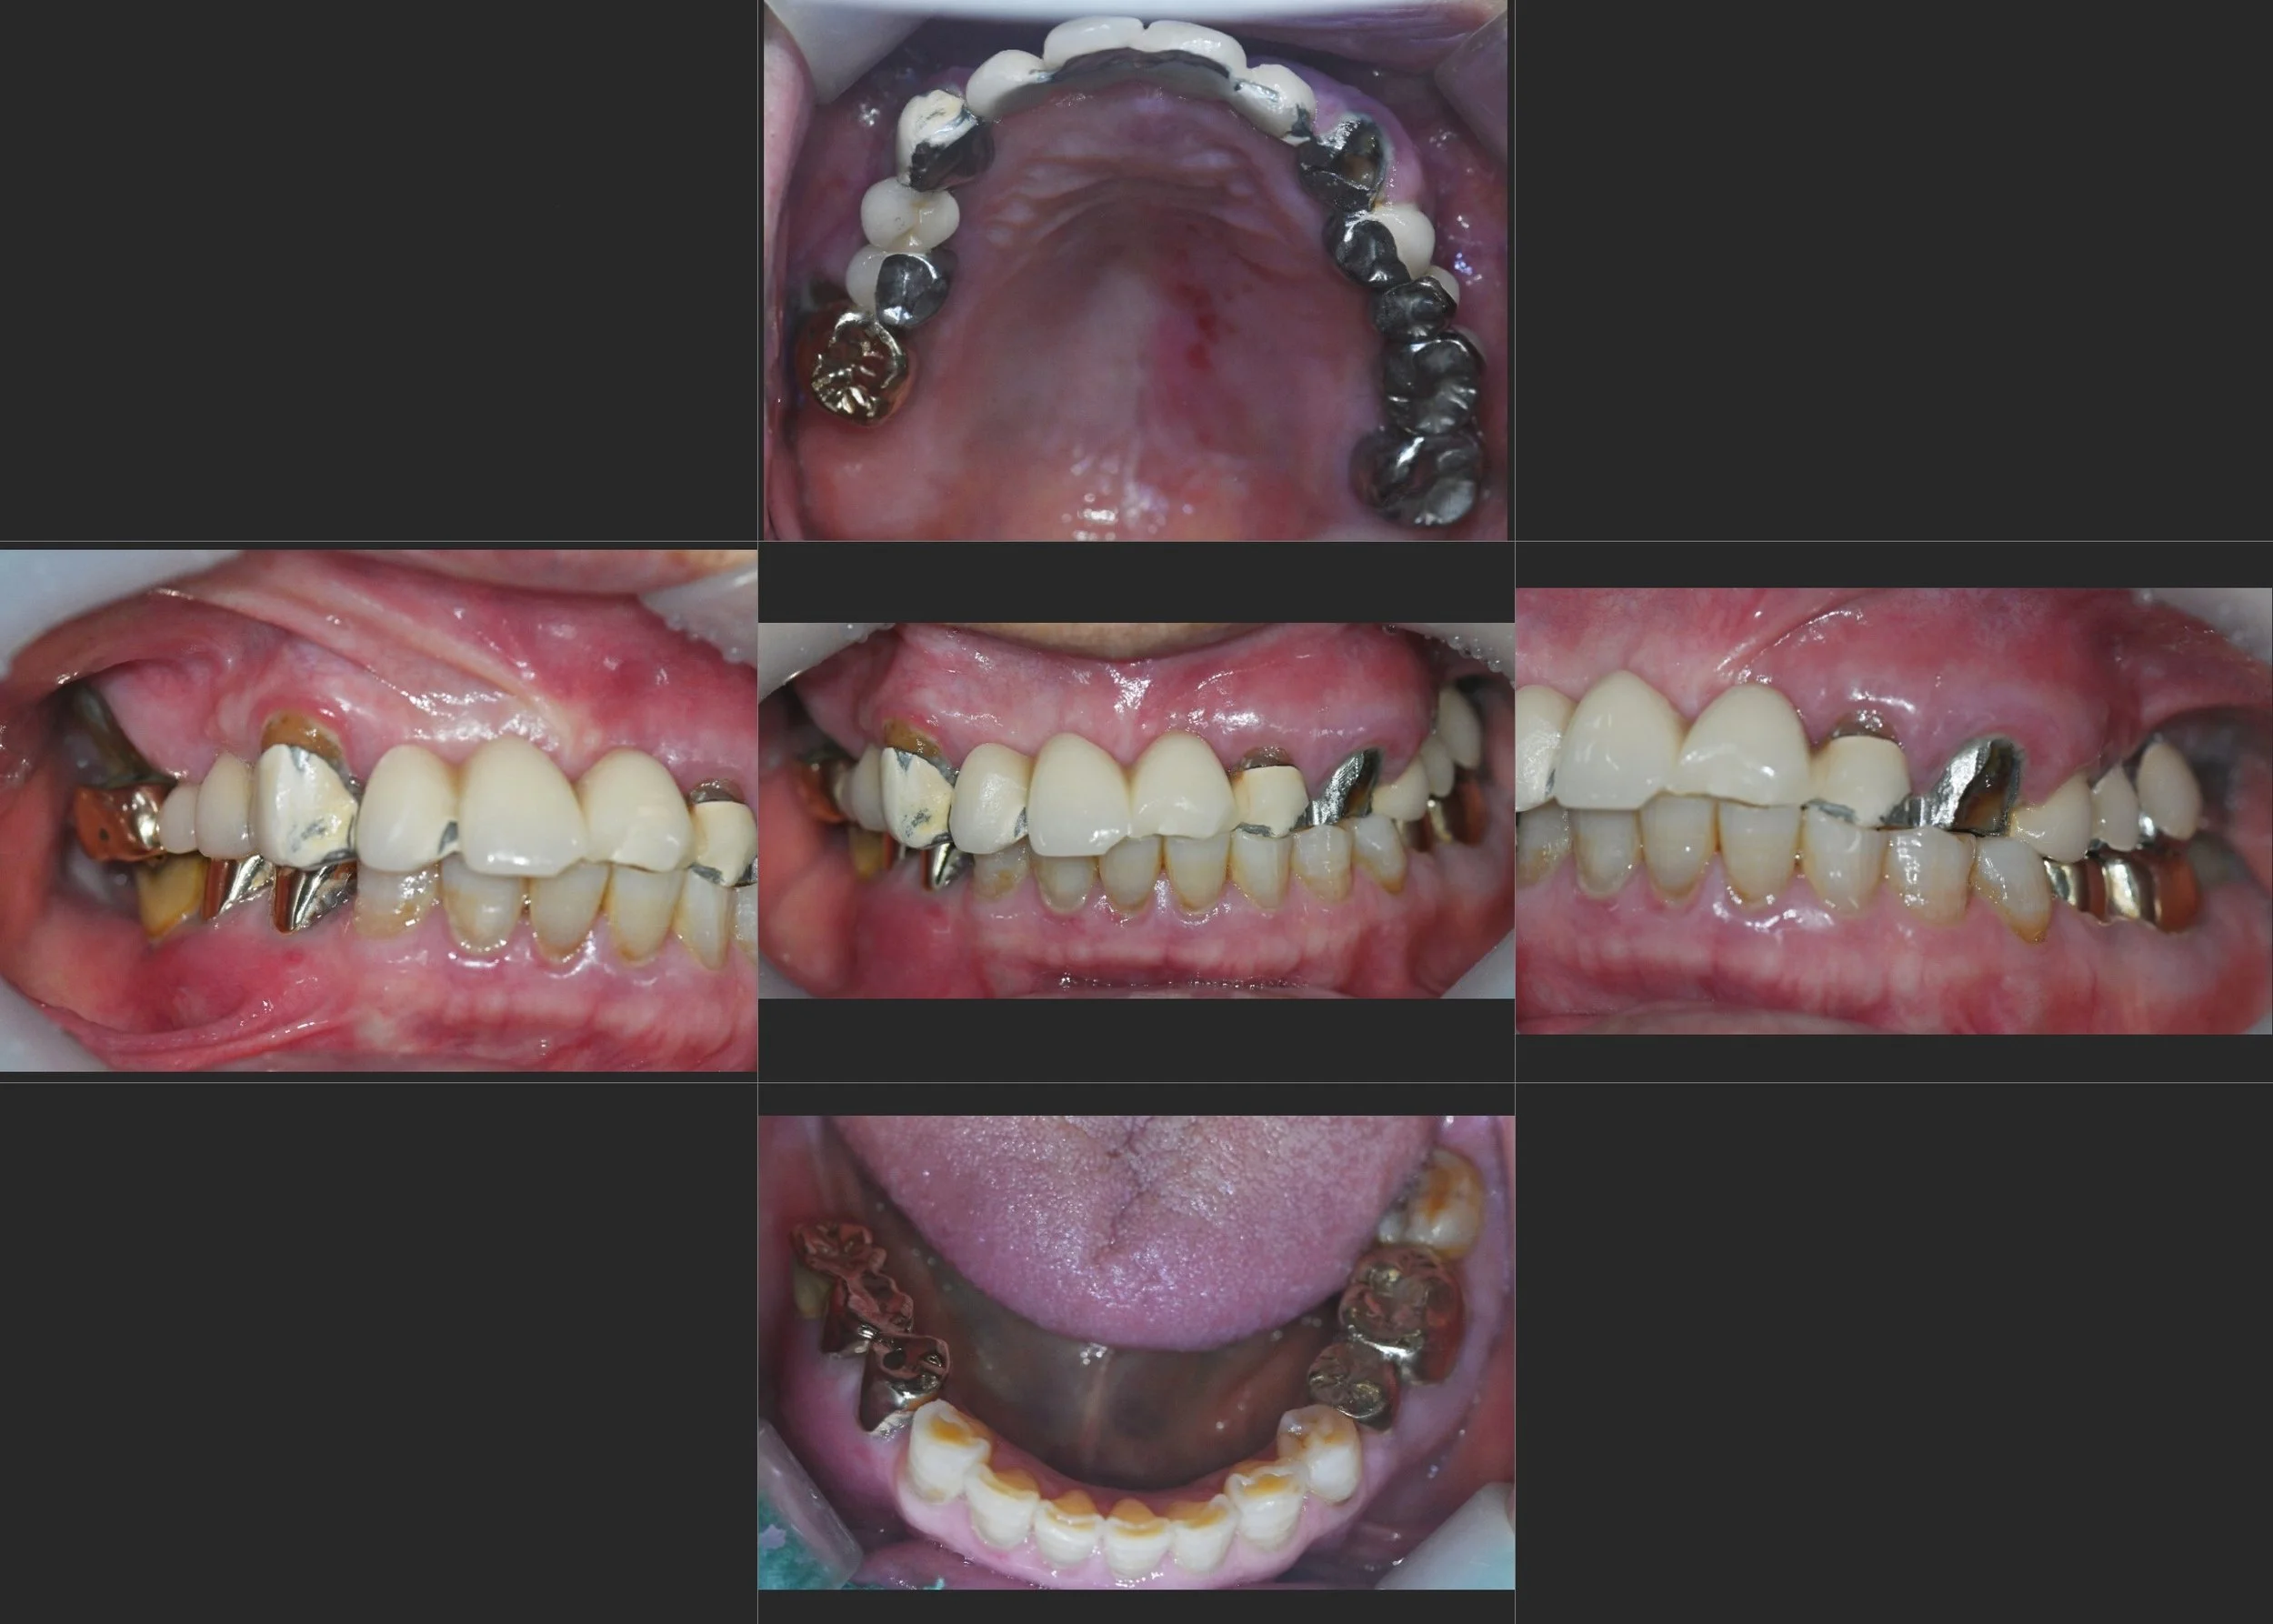

Contact

35. Comprehensive Full-Arch Transformation: Restoring Confidence in a Young Phobic Patient

Reversing the effects of generalized rampant caries and occlusal collapse in a female patient in her 20s. A tooth-preserving, implant-assisted approach focused on stable VDO elevation and overcoming social anxiety.